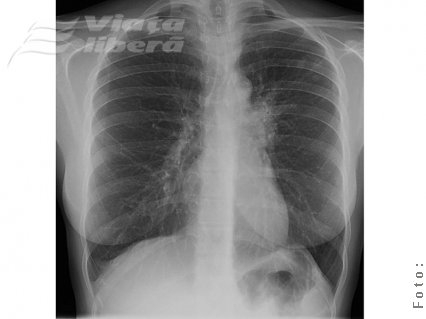

Cu chiu, cu vai reuşiseră să scape de chinul vieţii de la blocul G4 din Micro 20. Mai mult chiar, cu ajutorul medicilor de la Spitalul de Pneumoftiziologie Galaţi, bărbatul învinsese tuberculoza care îl chinuia.

Din nefericire, traiul greu şi-a pus amprenta şi asupra sănătăţii Valeriei, în vârstă de 30 de ani, care este acum internată, tot cu tuberculoză.